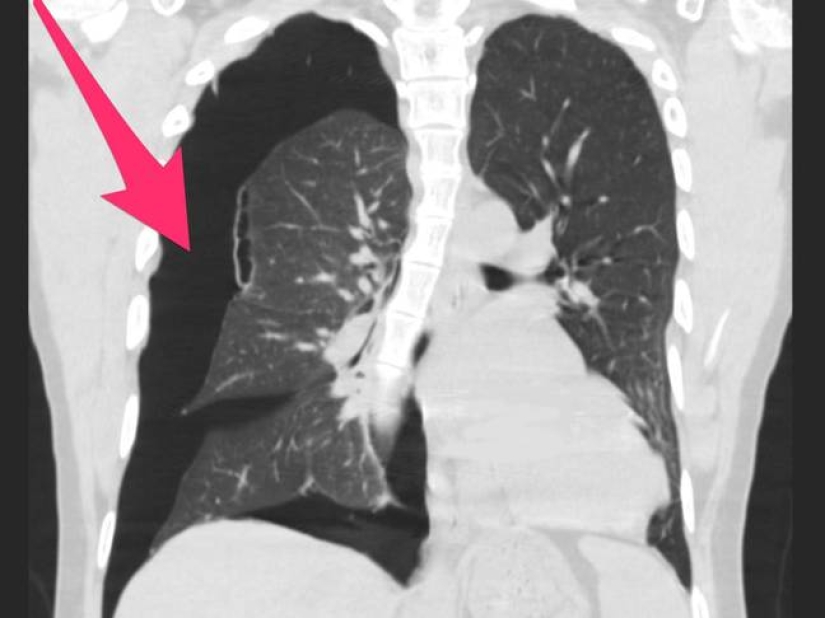

Los médicos decidieron publicar radiografías de los pulmones de los fumadores después de una serie de muertes asociadas con el uso del vapeo para advertir a todos sobre su daño.

Un pasatiempo de moda lleva a los jóvenes a la tumba, que están felices de inhalar humo fragante. Inofensivo, a primera vista, el enamoramiento conduce a consecuencias irreversibles. Las radiografías de los pulmones de los fumadores de vape son una prueba irrefutable del daño de las cachimbas electrónicas. Esperamos que esta información aparezca en su cabeza antes de la próxima calada.